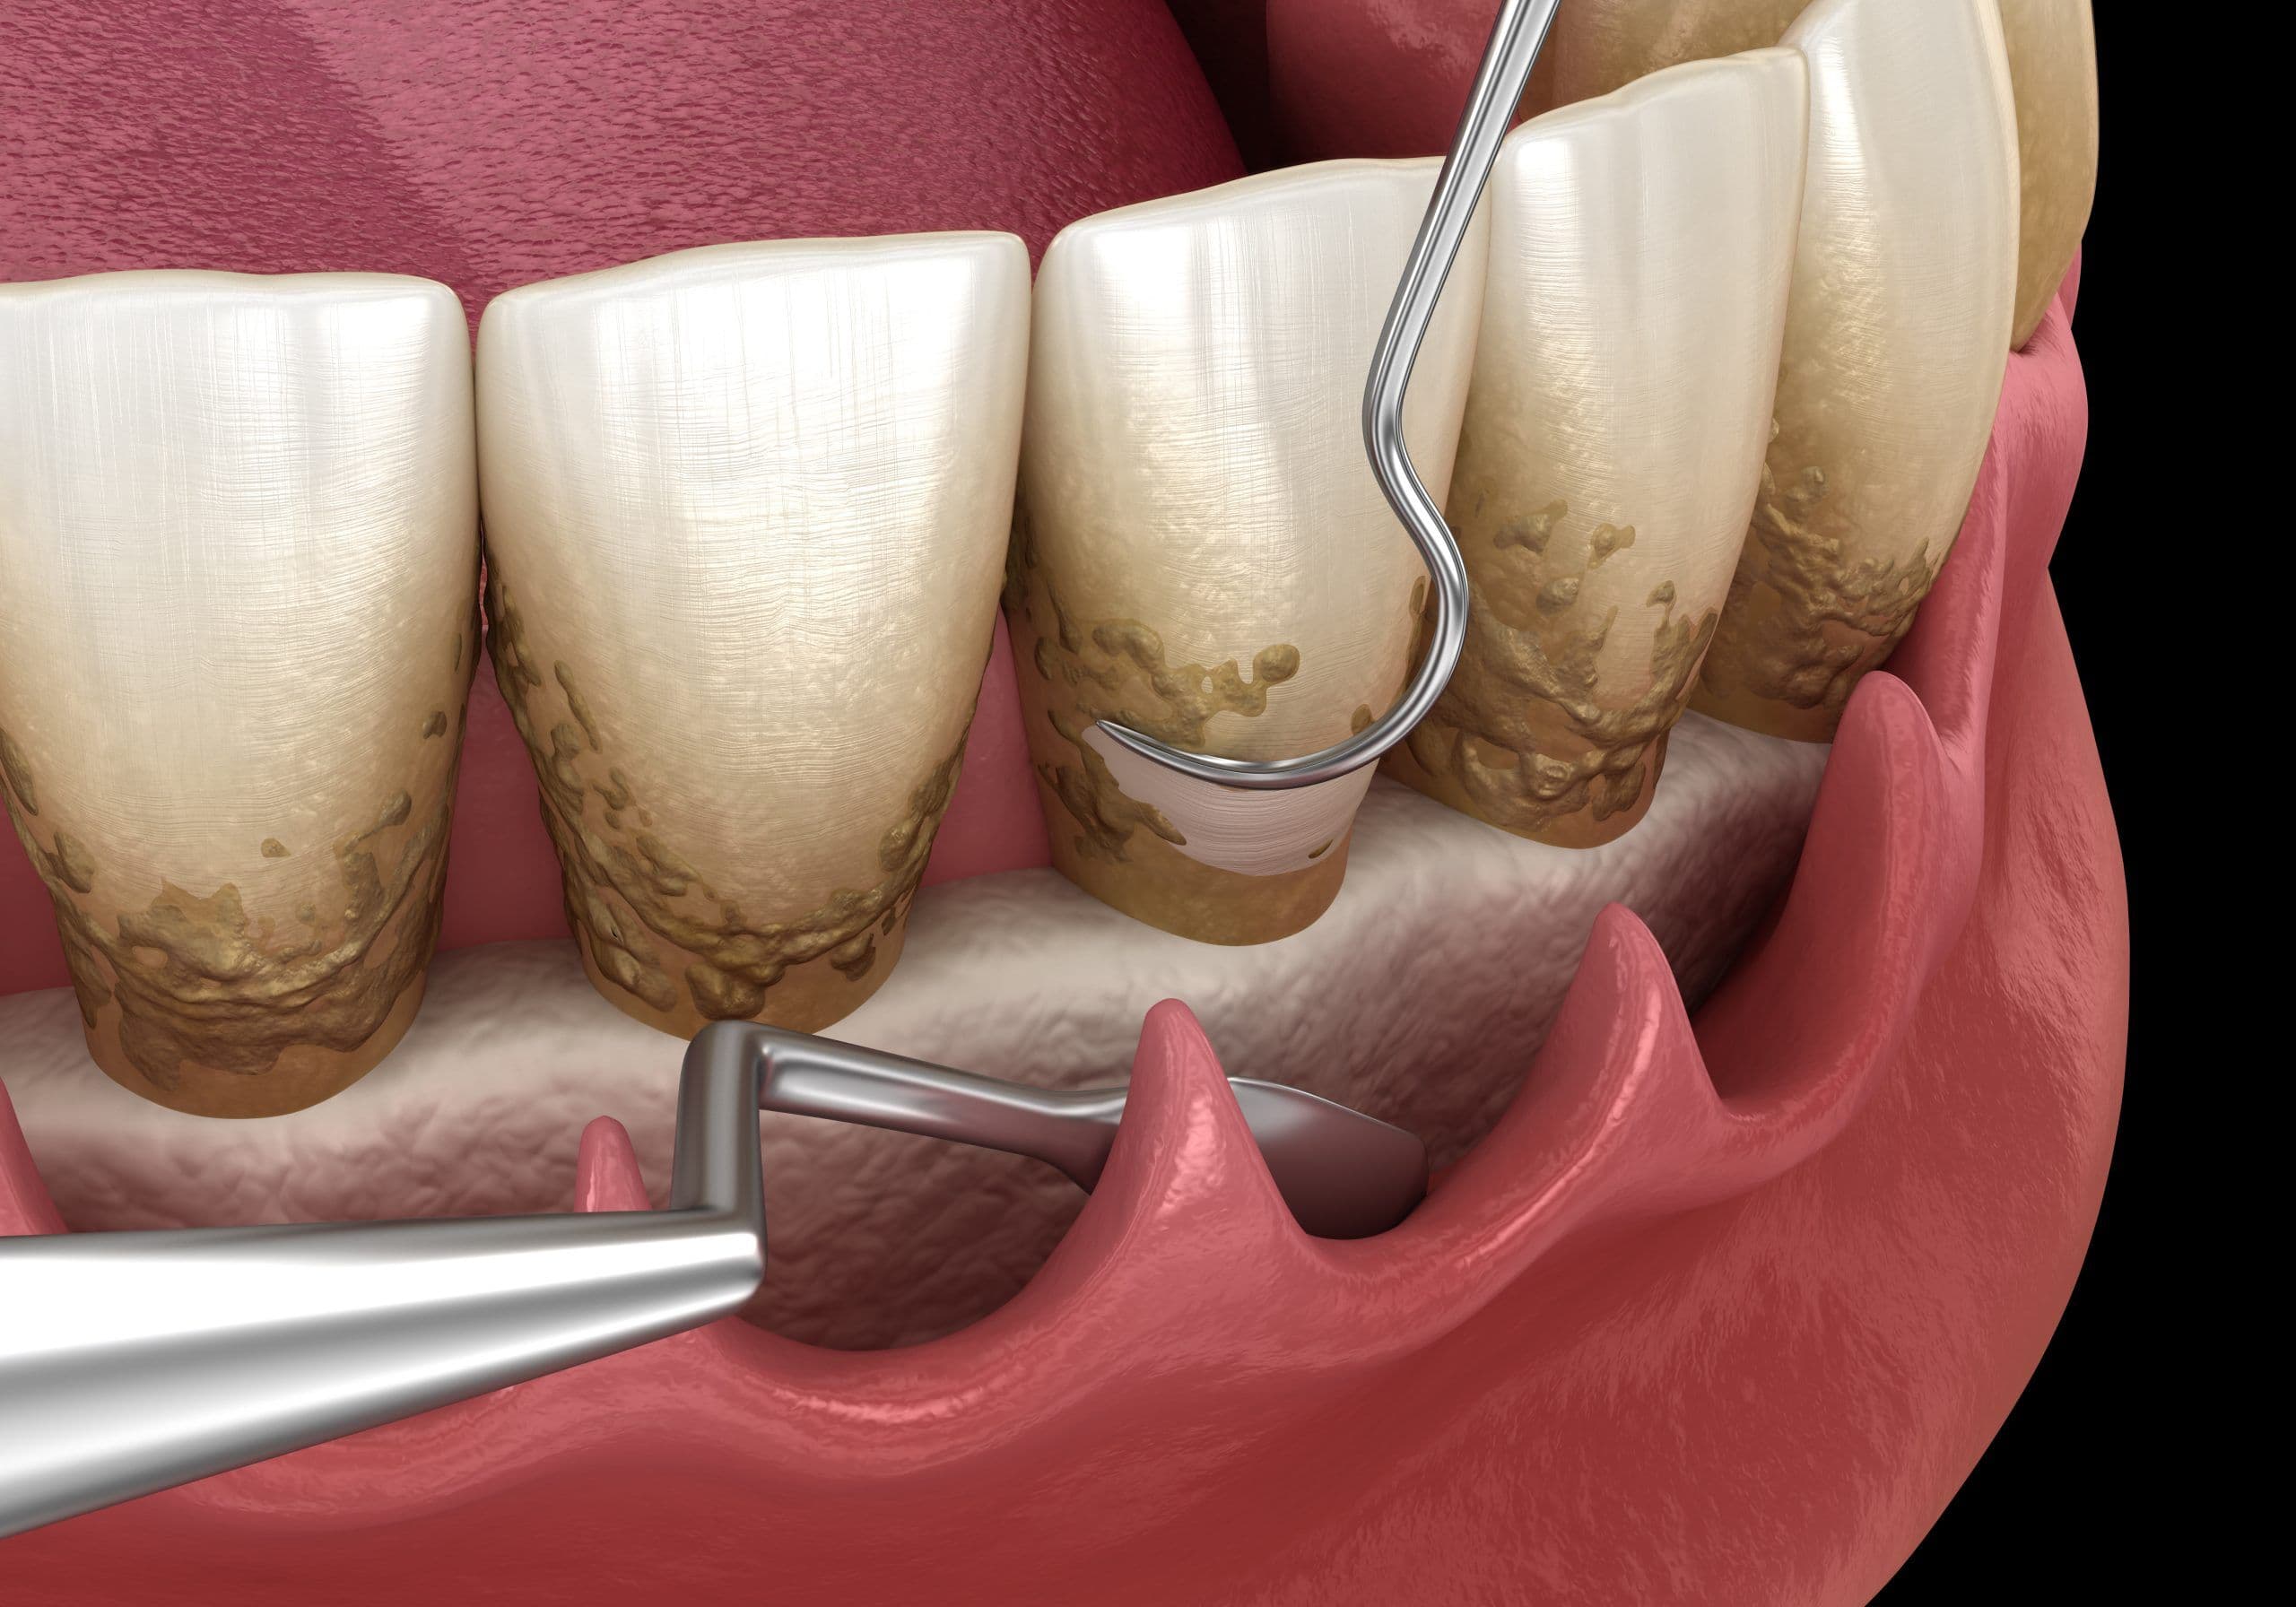

Фото и примеры имплантации зубов при пародонтите

Раздел: Необычные решения